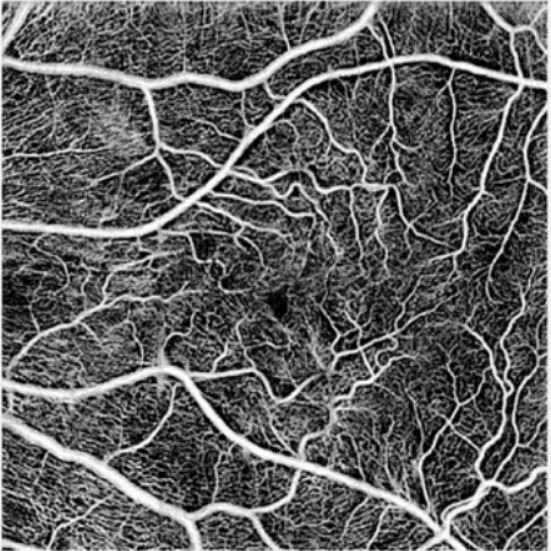

Ultra-high resolution, wide-angle imaging Clear visualization of ocular fundus vessels

High definition vascular microcirculation imaging Function integration

- High-resolution fundus imaging